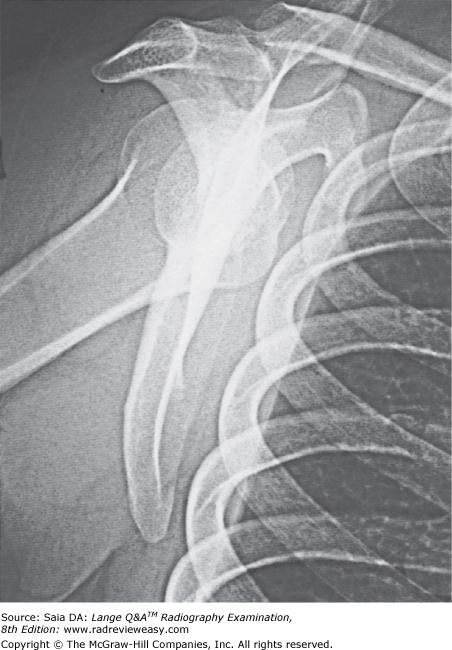

In which position of the shoulder is the outline of the greater tubercle superimposed on the humeral head?

A AP

B External rotation

C Internal rotation

D Neutral position

-The external rotation position is the true AP position and places the greater tubercle in profile laterally and places the lesser tubercle anteriorly. The internal rotation position demonstrates the lesser tubercle in profile medially and places the humerus in a true lateral position; the greater tubercle is seen superimposed on the humeral head. The epicondyles should be superimposed and perpendicular to the IR. The neutral position places the epicondyles about 45 degrees to the IR and the outline of the greater tubercle superimposed on the humeral head.